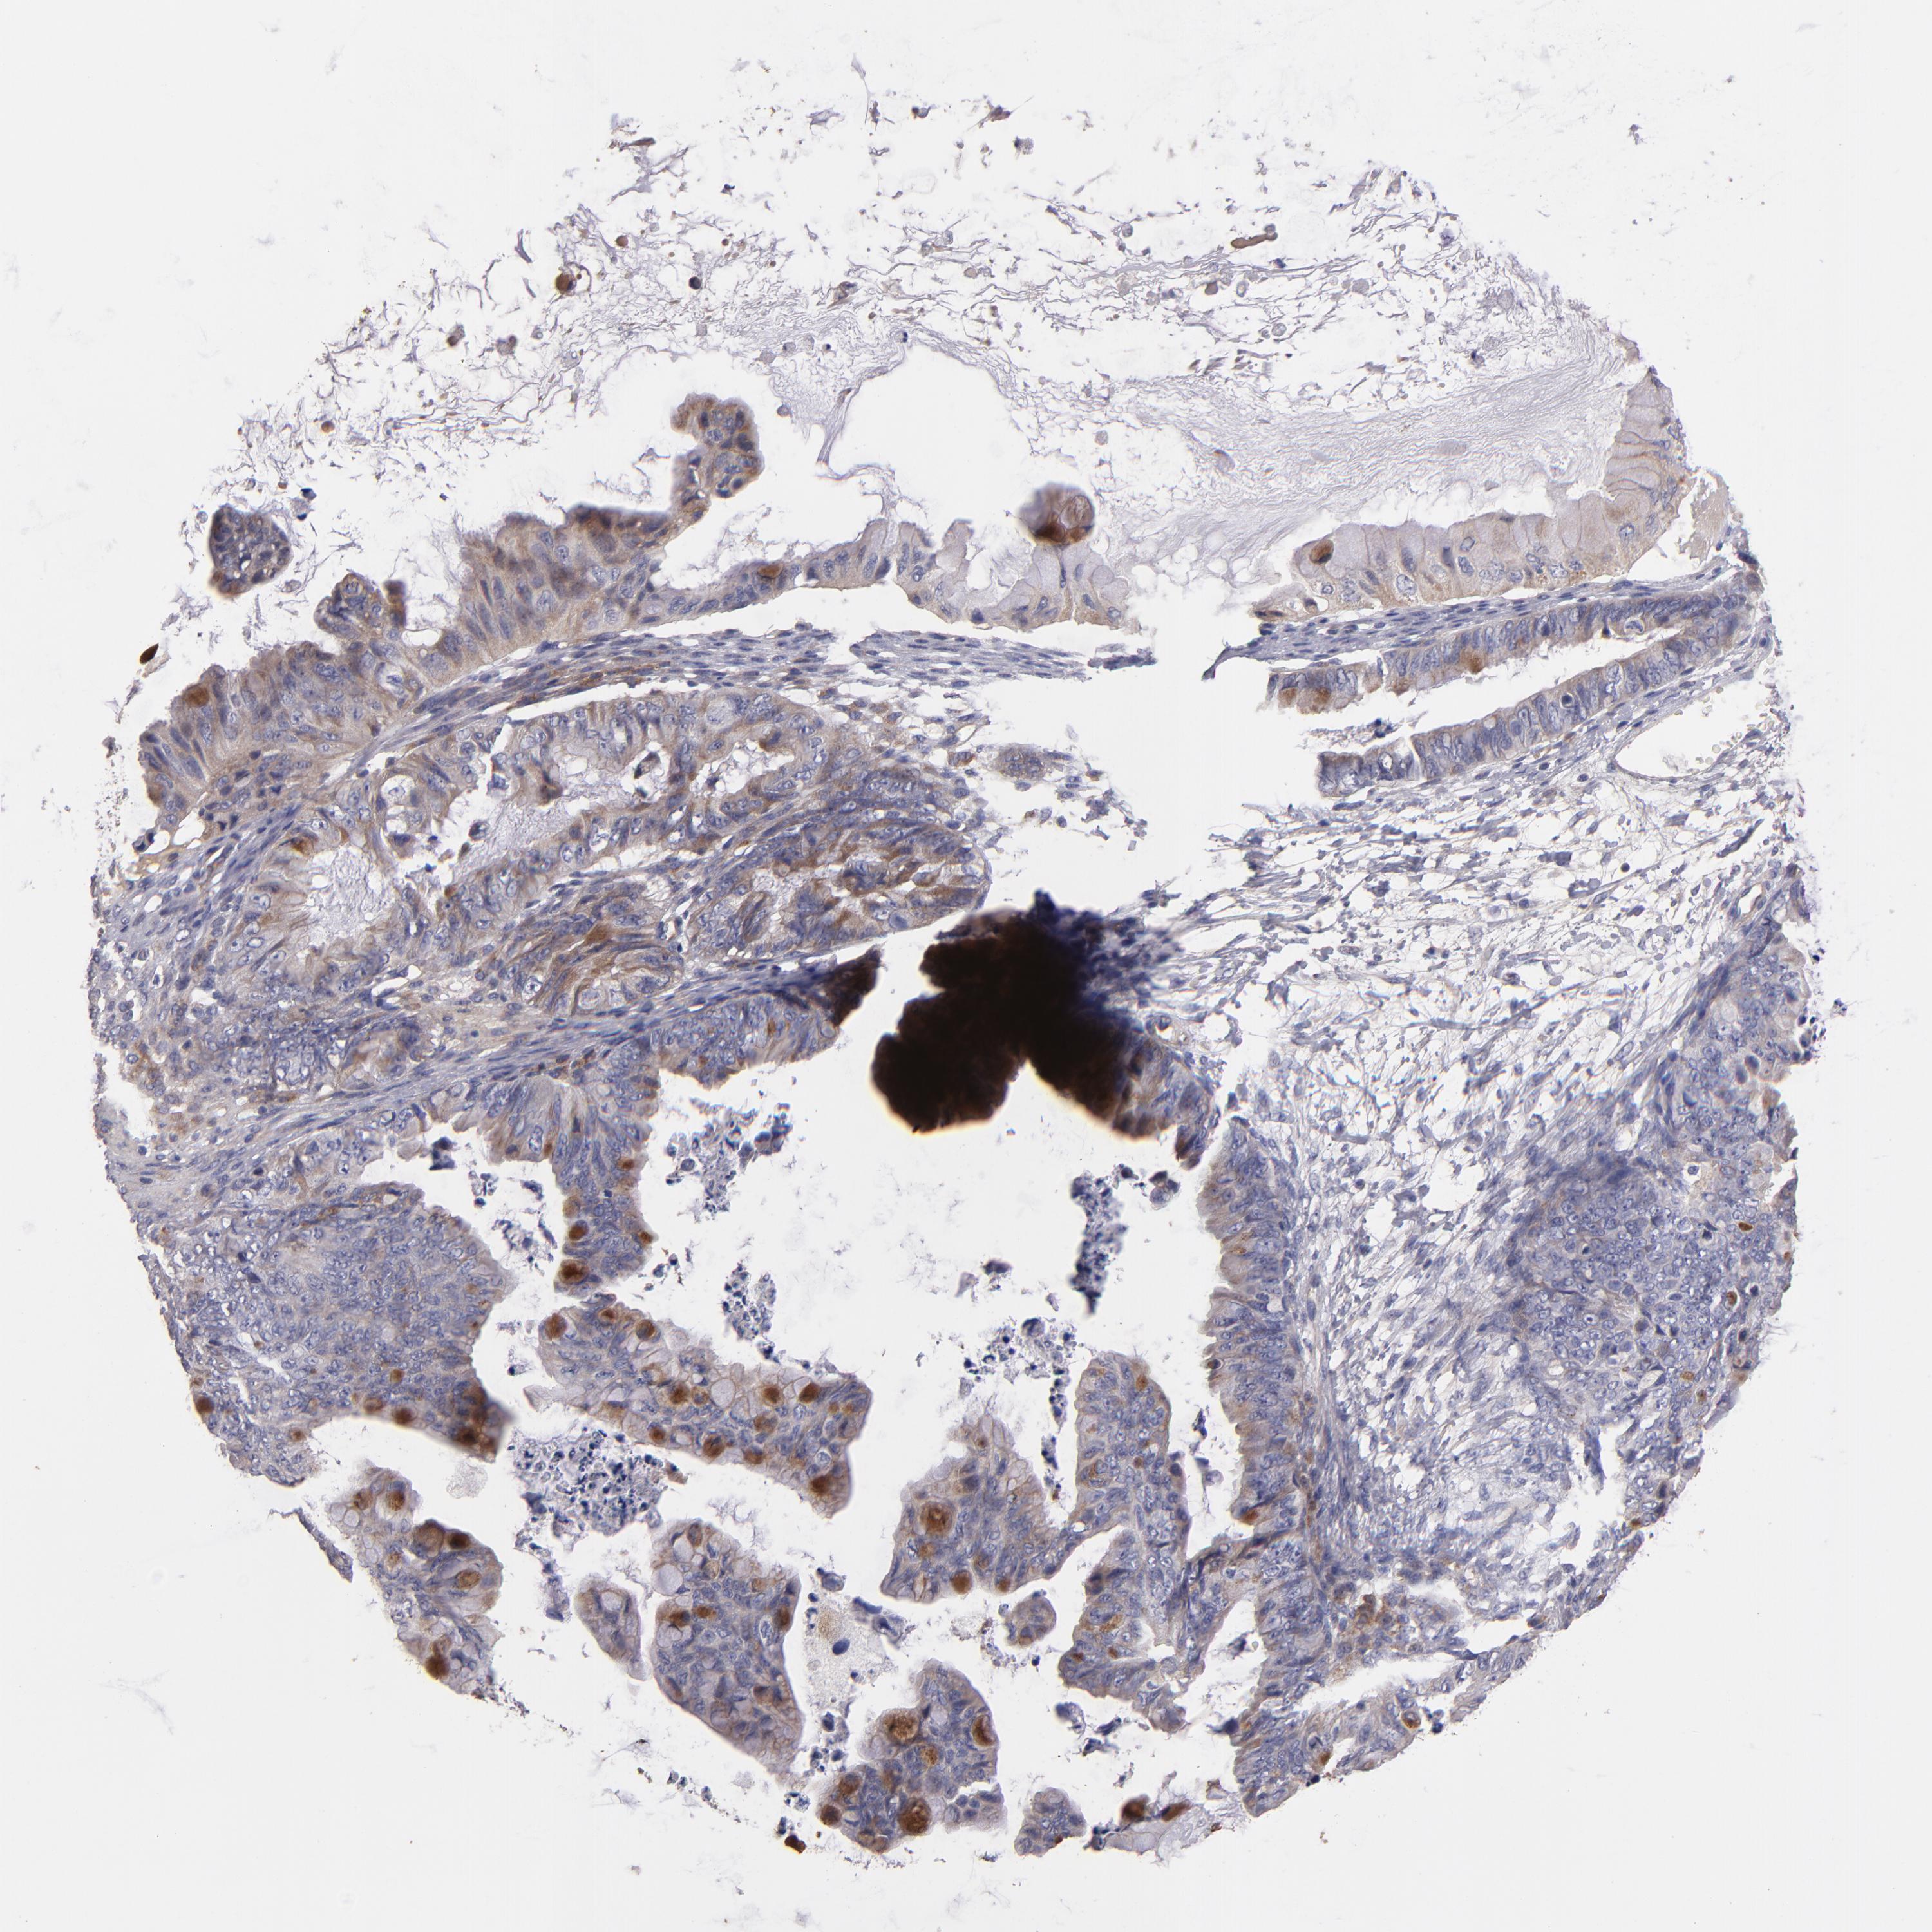

OVARIAN CANCER - Protein expressioni

A mouse-over function shows sample information and annotation data. Click on an image to view it in a full screen mode. Samples can be filtered based on level of antibody staining by selecting one or several of the following categories: high, medium, low and not detected. The assay and annotation is described here.

Note that samples used for immunohistochemistry by the Human Protein Atlas do not correspond to samples in the TCGA dataset.

Antibody stainingi

Antibody staining in the annotated cell types in the current human tissue is reported as not detected, low, medium, or high, based on conventional immunohistochemistry profiling in selected tissues. This score is based on the combination of the staining intensity and fraction of stained cells.

Each image is clickable and will lead to virtual microscopy that enables deeper exploration of all samples and also displays staining intensity scores, fraction scores and subcellular localization as well as patient and tissue information for each sample.

Antibody HPA003047

Staining

High

Medium

Low

Not detected

Intensity

Strong

Moderate

Weak

Negative

Quantity

>75%

75%-25%

<25%

None

Location

Nuclear

Cytoplasmic/membranous

Cytoplasmic/membranous,nuclear

Cystadenocarcinoma, serous, NOS

Cystadenocarcinoma, mucinous, NOS

Carcinoma, endometroid